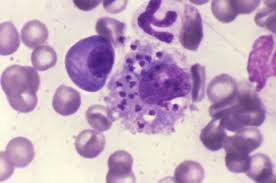

leishmania donovani stadia amastigota

leishmania donovani stadia amastigota